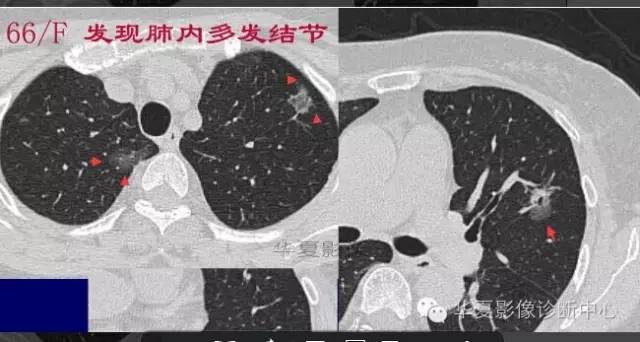

大家仔细看看这个中央不强化的腔内壁

你会发现内壁强化明显,边界清楚

一般这是炎性的脓腔,内层是肉芽肿,明显强化,分界清楚

癌肿的坏死一般是缺血性的,是肿瘤生长速度过快,中央带的血管受挤压,中央供血不足坏死的,一般边界模糊

内有内层强化,不会这么清楚

这是两者坏死的差异

内带强化带,边界清楚

但是这个其实整体看起来不是分叶征

只是一个一个的凸起